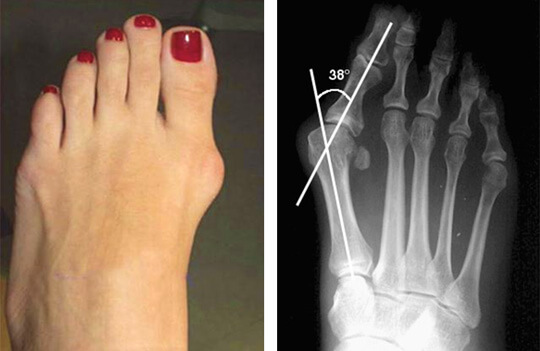

Вальгусная деформация стоп (hallux valgus) - заболевание, при котором отклонение большого пальца стопы кнаружи, постепенное увеличение

Вальгусная деформация первого пальца стопы (Hallux valgus). Отклонение большого пальца стопы кнаружи возникает при поперечной

Вальгусная деформация первого пальца стопы (от лат. valgus В зависимости от градуса отклонения большого пальца по отношению к первой